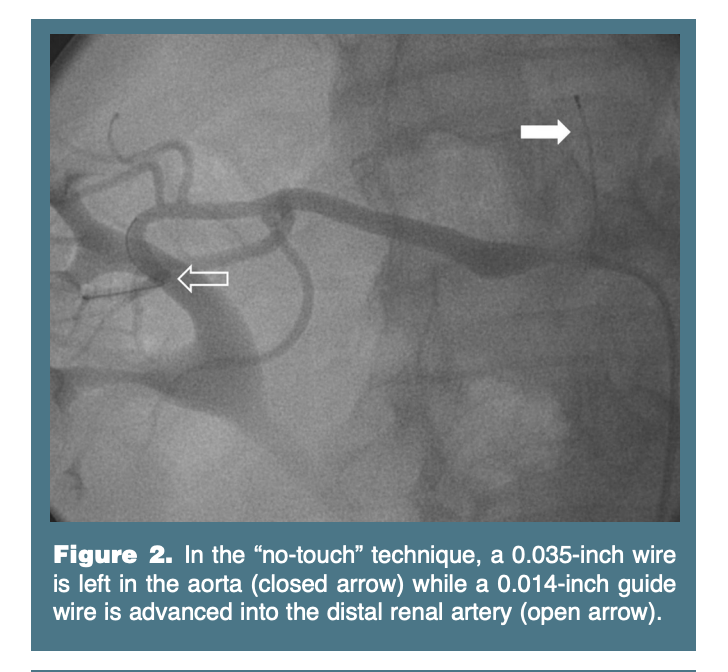

The goal of renal artery intervention is to achieve an optimal angiographic and hemodynamic result, with minimal manipulation of the renal artery in an effort to reduce atheroembolic complications. The “no-touch” technique may be used to minimize atheroembolization. In this technique a 0.035-inch guide wire is advanced in the abdominal aorta superior to the renal arteries. Over this wire, the guide catheter is advanced in proximity to the renal artery (Figure 1). The 0.035-inch wire is then retracted to the soft portion of the wire so that the guide catheter begins to assume its shape and approach the ostium of the renal artery. From this position, a 0.014-inch wire is directed through the guide and into the distal renal artery (Figure 2). The 0.035-inch wire is then removed and the guide catheter is then allowed to gently engage the ostium of the renal artery. Alternatively, the “telescoping technique” uses a diagnostic catheter introduced through a guide catheter to engage the renal artery. The guide catheter may then be advanced over the diagnostic catheter for atraumatic engagement.